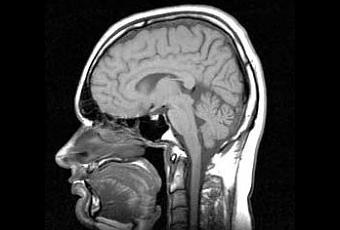

En el estudio, los investigadores midieron los niveles de más de 30 nutrientes en la sangre de 104 personas con una edad promedio de 87 años. En el total, los participantes eran bien educados, sanos no-fumadores que tenían relativamente pocas enfermedades crónicas y no tenían problemas con la memoria o el pensamiento. Los investigadores también realizaron escaneos mediante resonancia magnética de 42 participantes para medir el volumen cerebral.

Cierto grado de atrofia cerebral, o encogimiento, ocurre a medida que se envejece. El encogimiento más significativo se asocia a la enfermedad de Alzheimer.